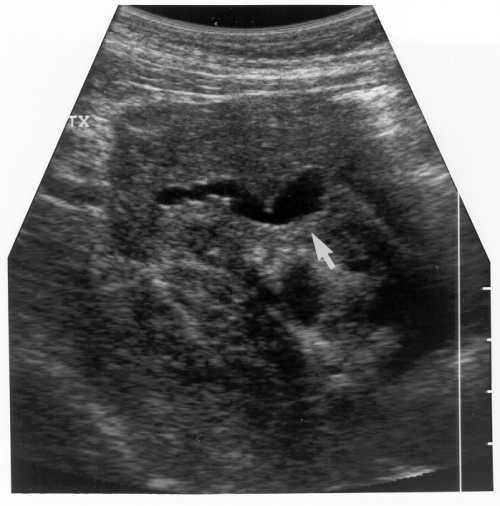

Case 1. A 38-year-old female underwent SPK. She lost kidney function due to an ischemic event (cortical necrosis by biopsy) and received a second kidney transplant (2 Dr match) 3 months later. Induction immunosuppression for the kidney included steroid bolus and recycling, and FK506 i.v. without antibody induction. She remained normoglycemic with normal serum and urine amylase. Six months later, after two kidney biopsy-proven acute rejection episodes, her creatinine was 1.4 mg/dl, but she was readmitted due to decreased urinary amylase (almost absent) and hyperglycemia for which she required insulin. US on admission demonstrated a dilated allograft pancreatic duct 10.3 mm (Figure 1). This improved with Foley catheter insertion. Video-urodynamics showed reflux into the pancreatic duct (Figure 2) and voiding in a not "relaxed manner" with evidence of pseudodyssynergia (Figure 3). Pancreas biopsy showed fibrosis without rejection. This patient requires insulin.

Figure 1. Ultrasound evaluation showed the pancreas transplanted in the right iliac fossa. A tubular structure was identified within the transplanted pancreas, which likely represented a dilated pancreatic duct. This structure measured 10.3 mm in transverse dimension. |